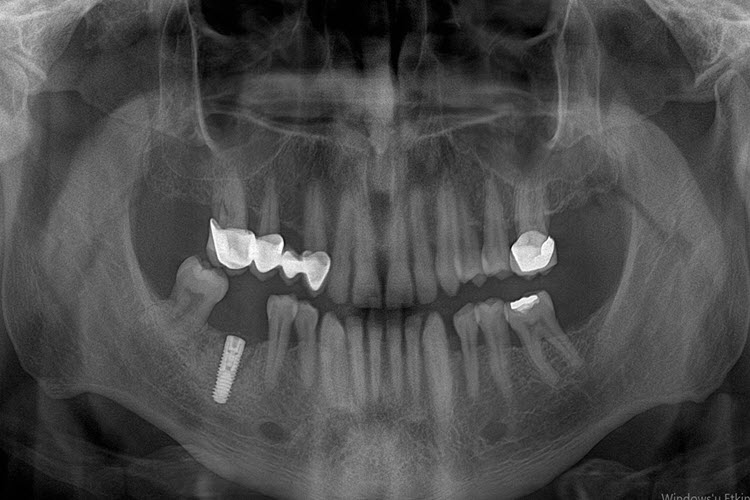

Dental implant, diş eksikliği varlığında hastaya yeniden çiğneme fonksiyonu ve estetik kazandıran titanyum alaşımdan üretilmiş, biyouyumlu bir vidadır. Çene kemiğine yerleştirilir ve diş kökünü taklit eder.

Tek diş eksikliği, çoklu diş eksiklikleri ve tam dişsizlik durumunda implant destekli protezler uygulanabilir. Uygulama öncesinde hastanın diş eksikliğinin bulunduğu bölgedeki 3 boyutlu kemik hacmini ve kalitesini belirlemek amacıyla bilgisayarlı tomografi ile inceleme yapılır. Buna göre implant sayısı, genişliği, boyu ve nereye yerleştirileceği belirlenebilir. Operasyon genellikle lokal anestezi altında gerçekleştirilir fakat hasta tercihine bağlı genel anestezi altında da yapılabilir.

Operasyondan sonra, 2 hafta ile 4 ay arasında değişen sürelerde üst protezin işlemlerine başlanabilir. Kemik yetersizliği durumunda; implant yerleştirilmesiyle eş zamanlı kemik artırma işlemleri uygulandıysa bu süre 6 ayı bulabilmektedir.

All on four, all on six implant sistemleri; tam dişsiz vakalarda belirli açılarla yerleştirilen 4 ya da 6 adet implant üzerine aynı gün geçici protezin sabitlenmesini sağlamaktadır. Üç ay içerisinde daimi protez yapılmaktadır.